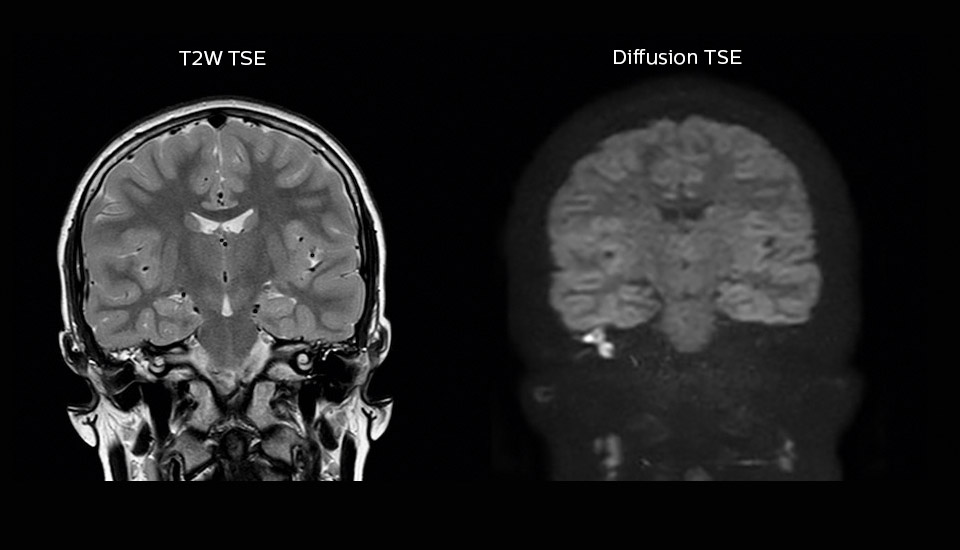

“Imaging cholesteatoma, benign tumors of the middle ear, has been a huge challenge,” says Dr. Heggelman. “We used to do CT, but then we were unsure if we were looking at an inflammation or a cholesteatoma. Also determining if residual cholesteatoma exist after surgery or visualizing recurrence used to be very difficult. Adding Diffusion TSE in our MRI protocol now effectively addresses this.” “Diffusion TSE is far less sensitive to susceptibility differences than previously used EPI sequences. We appreciate the high resolution and the robustness of the sequence. The quality is so good that our confidence has increased. Also our ENT (ear, nose, throat) physicians are excited about the high resolution, the excellent lesion delineation and the sensitivity and specificity.”